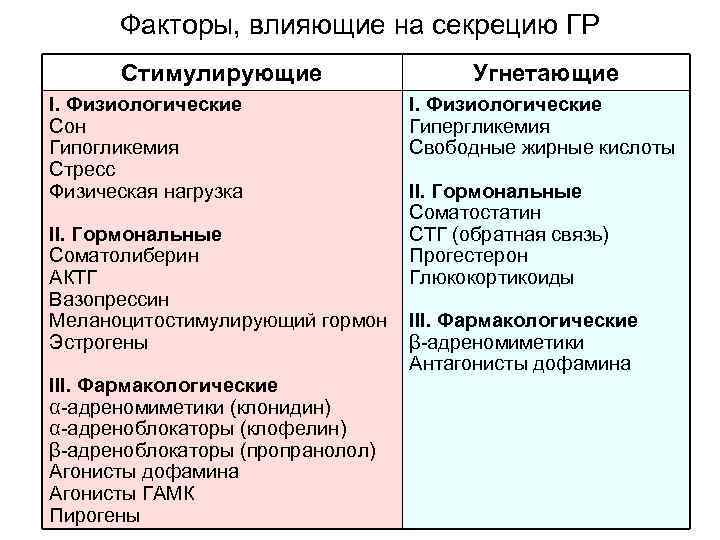

Факторы, влияющие на секрецию ГР Стимулирующие I. Физиологические Сон Гипогликемия Стресс Физическая нагрузка II. Гормональные Соматолиберин АКТГ Вазопрессин Меланоцитостимулирующий гормон Эстрогены III. Фармакологические α адреномиметики (клонидин) α адреноблокаторы (клофелин) β адреноблокаторы (пропранолол) Агонисты дофамина Агонисты ГАМК Пирогены Угнетающие I. Физиологические Гипергликемия Свободные жирные кислоты II. Гормональные Соматостатин СТГ (обратная связь) Прогестерон Глюкокортикоиды III. Фармакологические β адреномиметики Антагонисты дофамина

Факторы, влияющие на секрецию ГР Стимулирующие I. Физиологические Сон Гипогликемия Стресс Физическая нагрузка II. Гормональные Соматолиберин АКТГ Вазопрессин Меланоцитостимулирующий гормон Эстрогены III. Фармакологические α адреномиметики (клонидин) α адреноблокаторы (клофелин) β адреноблокаторы (пропранолол) Агонисты дофамина Агонисты ГАМК Пирогены Угнетающие I. Физиологические Гипергликемия Свободные жирные кислоты II. Гормональные Соматостатин СТГ (обратная связь) Прогестерон Глюкокортикоиды III. Фармакологические β адреномиметики Антагонисты дофамина